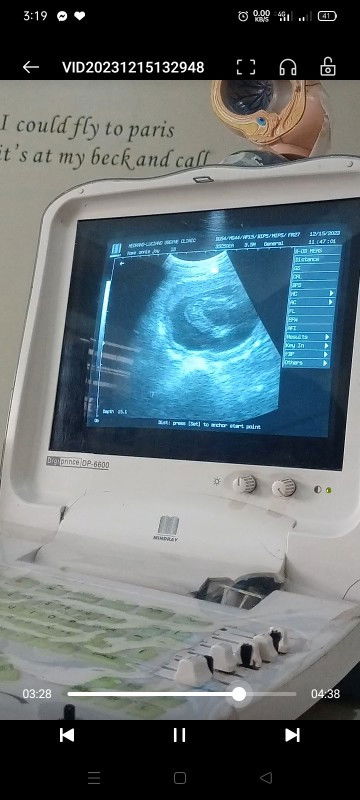

Im 7weeks pregnant po , Nirequest po ni doctor na magpaultrasound ako, Ang lumabas po na result sa US ay 5weeks and 6days at wala papong heartbeat na nadetect, at nung binasa po ni doctor sabe po e nakunan daw po ako . Possible po ba na magkamali sa ultrasound ? Kahit ramdam ko papo na buntis ako kase halos everyday nasusuka ako at lage ding nasakit ang dede ko . Thankyou po sa sasagot .#pleasehelp